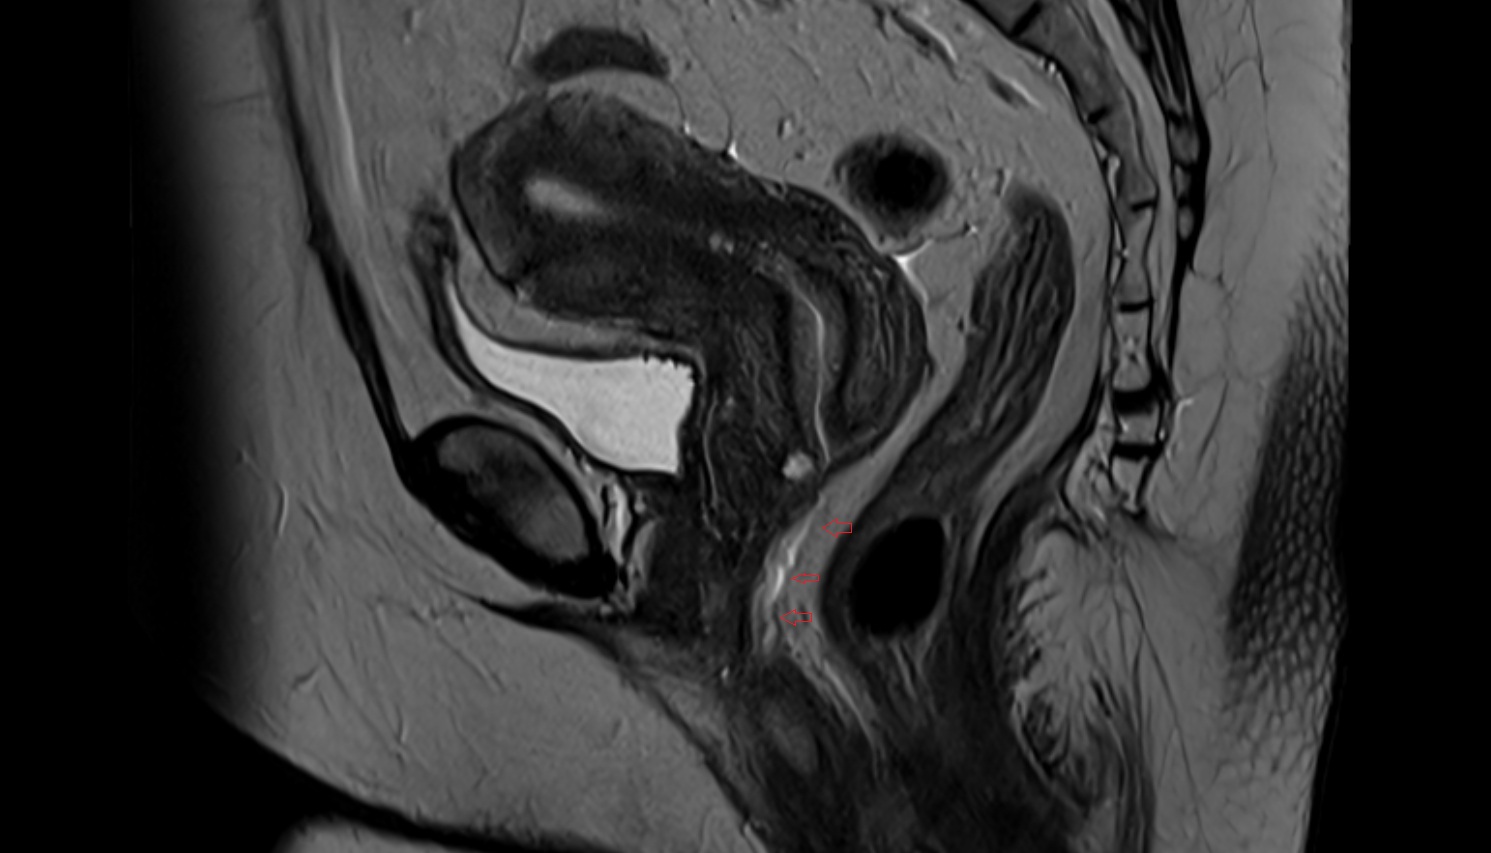

- Rectum

- Urinary bladder

- Uterus

- Body of uterus

- Fundus of uterus

- Cervix of uterus

- Isthmus of uterus

- Vagina

- Fornix of the vagina

- Vesicouterine pouch

- Rectouterine pouch (pouch of Douglas)